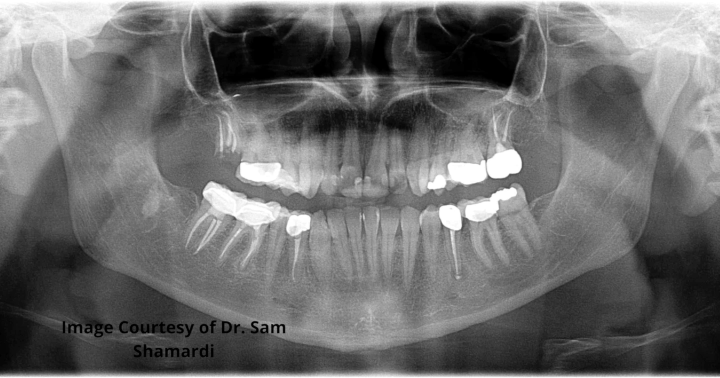

This month I had the privilege of working with periodontist Dr. Sam Shamardi. Patient procedure completed: Extraction of residual root tips from fracture of tooth no. 2 and crown lengthening for no. 3.

Crown lengthening procedure: results

Image courtesy of Dr. Sam Shamardi